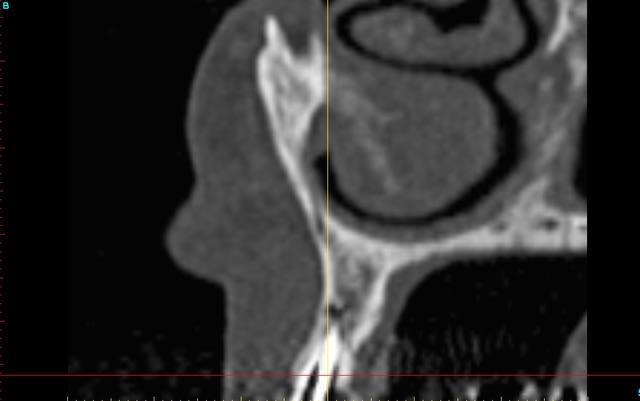

le scan n'est pas terrible, mais suffisant pour voir que 22 une fois extraite, ne va pas etre simple à implanter, par contre 11/21 avec un peu d'expansion...

Des lecross section21 jinha0 - Eugenol

Des lecross section sf6tbl - Eugenol

Des le cross section 12 vyz5ug - Eugenol

Des le cross section 22 w31w6b - Eugenol